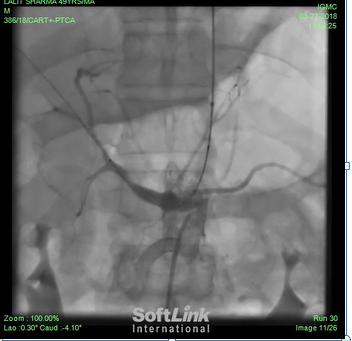

Management: heparin should be started in patients with AMI. Because of high risk of infection, antibiotics should be started. Oral intake is avoided as it can increase ischemia23. Thrombolytic therapy may be rewarding, if given within 8 hours of symptom onset, if signs of bowel necrosis and peritonitis are not there [24]. Revascularization is the cornerstone of treatment of AMI, otherwise the mortality is very high. In one study of 104 patients, mortality within 30 days was 64% n patients who were not revascularized, compared to 42% in vascularized patients[25]. Outcome in AMI is determined by intestinal viability. Non viable intestine may result in multi organ failure and ultimately may be fatal. So after initial stabilization laprotomy is performed, intestinal viability is assessed, non viable intestine is resected and revascularization is performed by means of embolectomy or arterial grafts. Nowadays endovascular procedures may be an alternative to surgery (figure 6-9). Though there are no head to head studies comparing surgery and endovascular approach in AMI, some studies show less need for surgery, less bowel necrosis and less mortality with endovascular approach26. However, open surgery helps in assessing the viability of the intestine and so taking appropriate decision, especially when endovascular approach is not available27. Patients with resection of large segment of small bowl can suffer from small bowel syndrome and intestinal failure, which is associated with poor quality of life[2]

Figure 6: Abdominal aortogram in a patient of AMI. SMA shows total cut off just after origin. Coeliac atery shows 95% stenosis at origun.

Figure 7: Stenting of SMA in same patient of AMI.

Figure 8: Stenting of celiac artery in the same patient of AMI.

Figure 9: Good result in both celiac artery and SMA after stenting. Patent had developed necrosis of 6 feet small intestine, for which surgical resection and temporary iliostomy was required after the stenting.